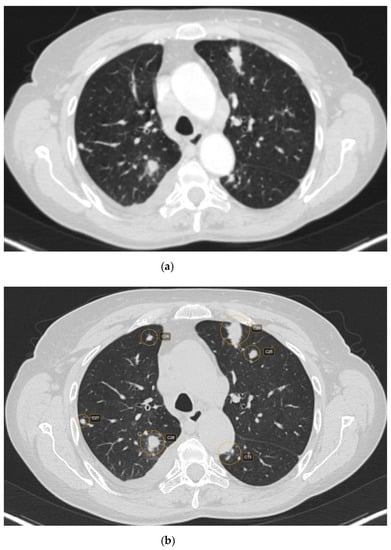

CT characteristics of the pulmonary rheumatoid nodules included smooth margins (p < 0.001) and a predominantly subpleural location (p = 0.045) (Figure 3). In addition, 87 (47.02%) nodules were cavitating, while calcifications were rare, evidenced in 18 (9.72%) nodules.

Figure 3. CT scan (lung window) showing raw CT images (a) versus marked CT images using CAD (b).